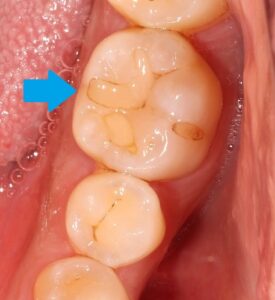

歯と歯の間の虫歯です。どこに虫歯があるか分かりますでしょうか?

虫歯の所を削ってみてみると・・・

歯と歯の間の中に茶色い虫歯がありました。

これは分かりませんね。